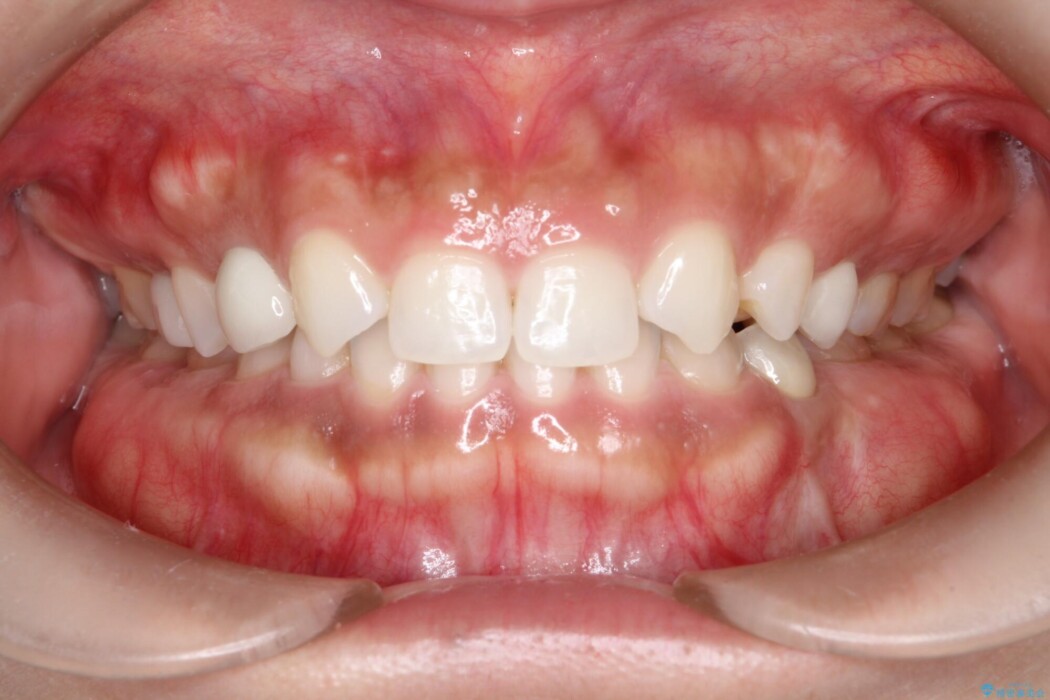

治療後について

噛みしめることができるようになったと喜んでいただきました。